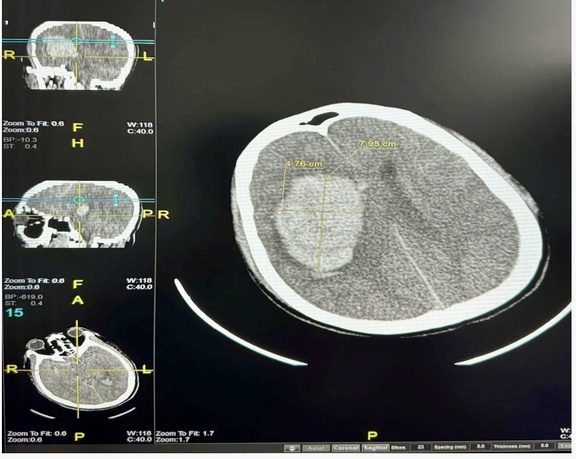

Hình ảnh phim chẩn đoán bệnh nhân Đ.V.Đ bị đột quỵ với khối máu tụ bán cầu phải với thể tích lớn

Trước đó, đêm 6.12, bệnh nhân Đ. được gia đình đưa vào cấp cứu trong tình trạng hôn mê sau khi tắm khuya. Kết quả chẩn đoán cho thấy, bệnh nhân bị xuất huyết não với khối máu khá lớn. Tình trạng này buộc các bác sĩ phải phẫu thuật mở sọ để giải ép áp lực não.